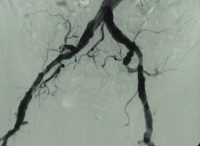

DSA preoperatoria del paciente:

PM 311-1

Abb. 1: Hochgradige Arteriosklerose der terminalen Aorta und der Beckenstrombahn bds.

PM 311-2

Abb. 2: Langstreckiger Verschluss der A. femoralis superficialis bds.